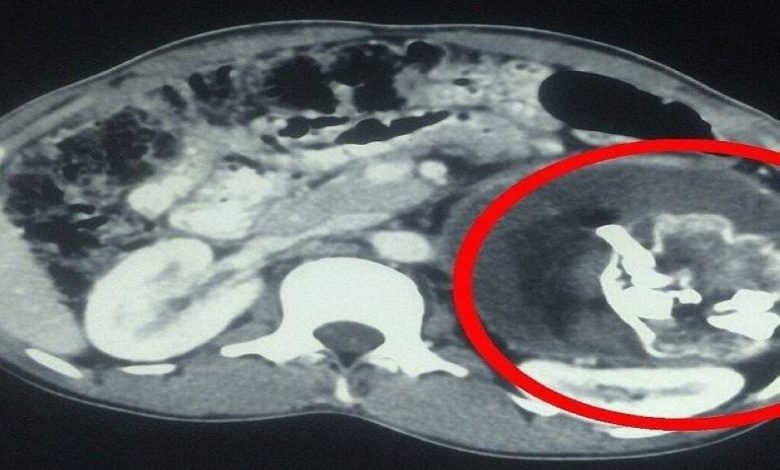

معجزة طبية.. استخراج «جنين طفيلي» من بطن رضيع